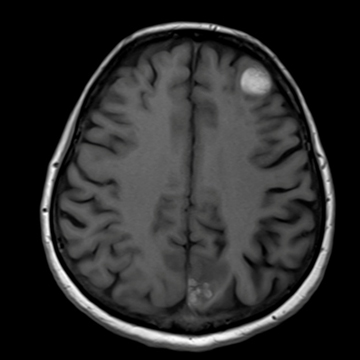

頭部ルーティーン

T2 TSE, matrix 512,

Dark Fluid, matrix 320,

腫瘍

Dark Fluid, 320 matrix

T1 FLASH, 320 matrix

Diffusion, b-value 1000, iPAT 2

T1 MPRAGE pc, iPAT 2

脳腫瘍